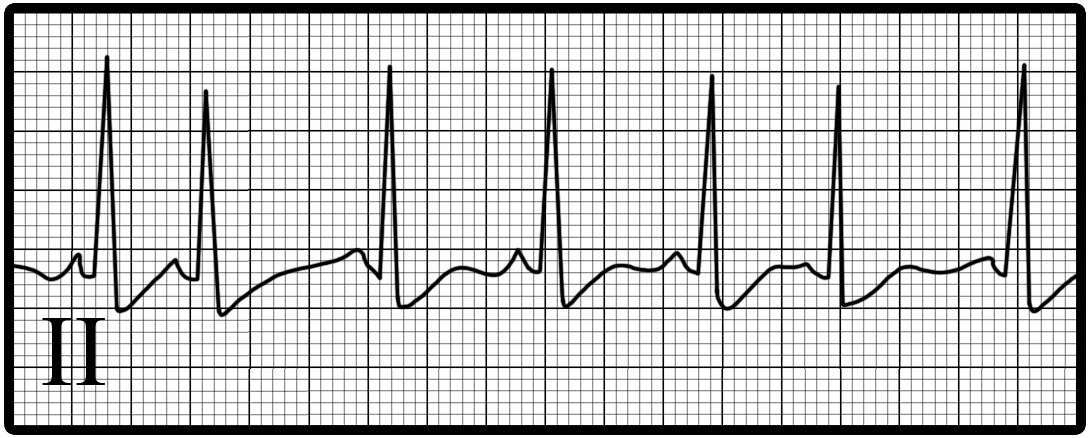

You are incorrect - The best interpretation of the rhythm strip in our patient is atrial fibrillation.

Your choice: Sinus rhythm with premature atrial complexes

This rhythm strip shows sinus rhythm with premature atrial complexes. The characteristic features demonstrated here include:

An underlying normal sinus mechanism with normal P waves followed by early QRS complexes preceding each QRS; and early, or premature, P waves the premature P waves most often differ in shape from the sinus P waves, while the premature QRS complexes most often are identical to the sinus QRS.

Isolated atrial premature complexes are benign.